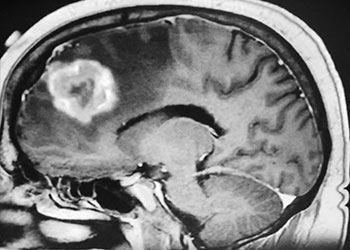

Figure 1: Sagittal post-contrast MRI. Figure 2: Axial post-contrast MRI. Postoperative images looked good (Figure 3). The patient felt better after surgery. His headaches were much […]

Dr. Brisman started the patient on steroids to reduce the surrounding edema. After a few days, the patient did note some improvement in her vision. Due […]